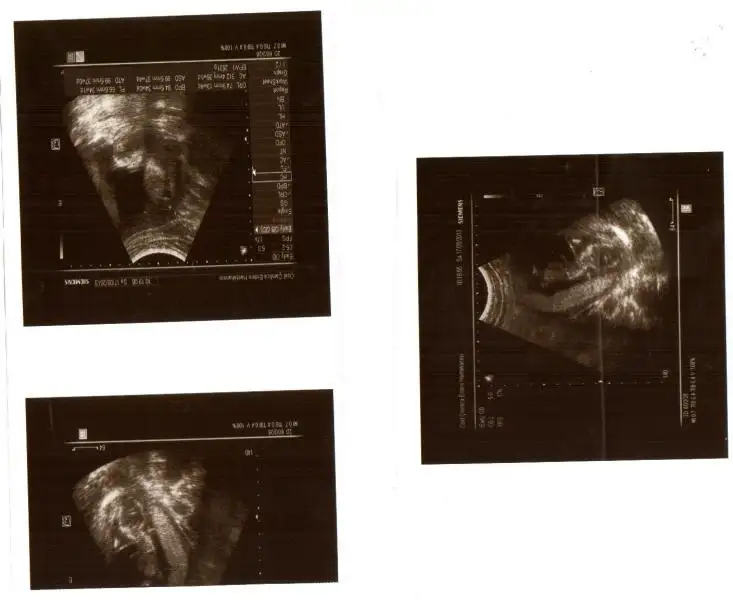

kızlar benim resimlerede bi yorum yapın ne acaba?ben anlayamadım.çabuk yazın çok merak ediyorum![]()

hayret bu resme gore kiz dr erkek demis gerci resim tamda net degil allhim tamamina erdirsin